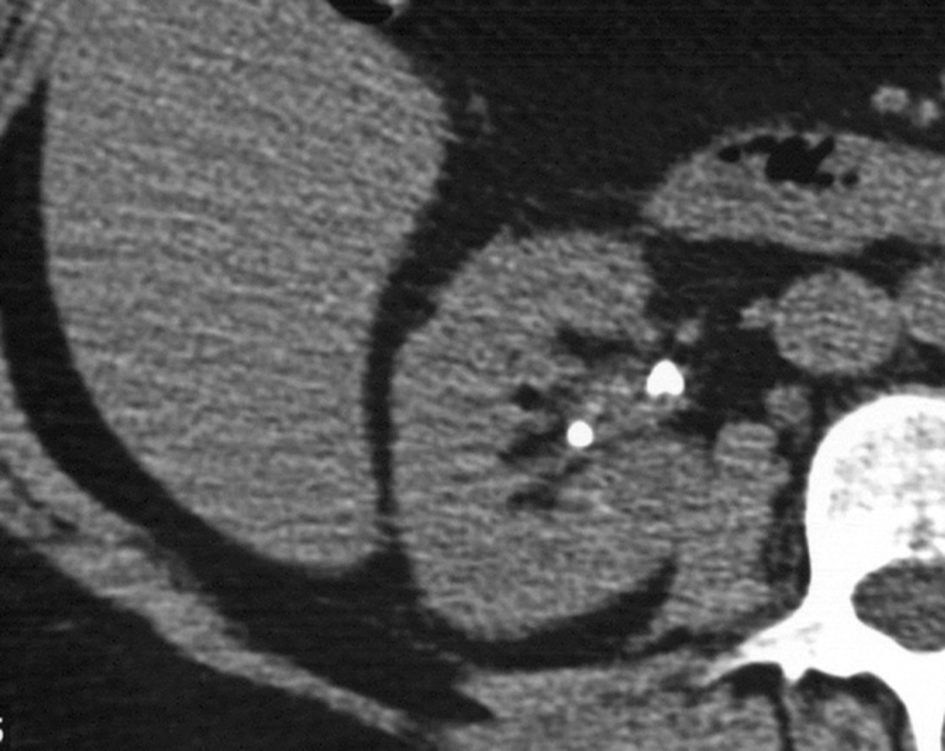

Fig. 24.1. Hématurie isolée.

Découverte de deux petits calculs de faible densité (calcul d’acide urique) sans dilatation des cavités excrétrices (scanner avant injection).

Source : CERF, CNEBMN, 2022.